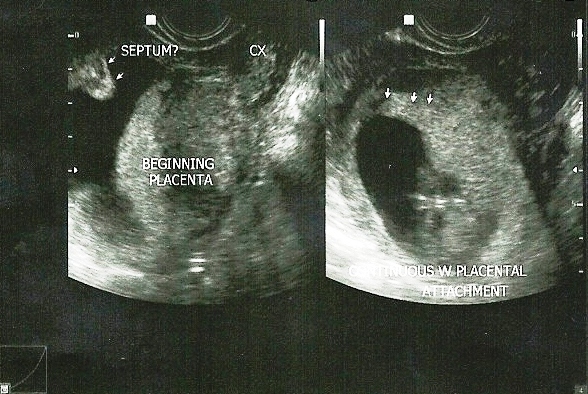

Isn't it ironic that after my mental, physical and emotional preparation for a natural birth, my doctor said that she needs to do a Hysteroscopic removal of my uterine septum?

Yes, a septum can be resected with surgery. In this way, I'm being prepared for the next baby. We need to do this procedure to avoid any other problems in my next pregnancy (should we decide to get pregnant again). It is known that a septum is associated with a higher risk for miscarriage, premature birth, and malpresentation. According to the classical study by Buttram there is a 60% risk of a spontaneous abortion, this being more common in the second than in the first trimester. There are a lot of cases that a septum has not caused any problems and thus may not be removed but since I experienced a miscarriage before, my doctor would want to avoid that next time. Also, it's for our own peace of mind.